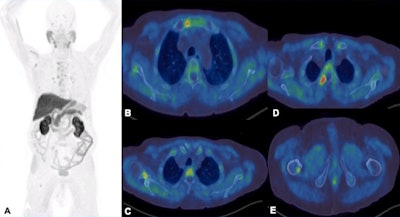

F-18 choline tracers are taken into cells by choline transporters. They are subsequently phosphorylated by choline kinase, which is overexpressed in tumors, and finally the tracers are incorporated into cell membranes. They can identify skeletal, marrow-based, and extraskeletal disease, and they have high sensitivity and specificity, for instance compared with a bone scan, and can be useful in assessing treatment response and restaging, the authors wrote.

However, the sensitivity of the test is influenced by prostate-specific antigen (PSA) levels, and sensitivity increases with higher PSA levels. Also, sensitivity -- and therefore detection rate -- of microcarcinoma is limited by partial volume effect, negative scans do not rule out metastasis, and uptake in densely sclerotic bone lesions is inconsistent, especially after therapy. False positives may occur in recent traumas and fractures.

Prostate-specific membrane antigen (PSMA) tracers are superior to choline tracers in detecting prostate malignancy at low PSA levels, and they can detect both osseous and extra-osseous metastasis, the authors wrote. Also, they have a higher signal-to-noise ratio compared with F-18 choline, and they outperform bone scans in detection of affected bone regions and assessment of overall bone disease volume. Furthermore, they have higher sensitivity, specificity, and overall accuracy in detecting skeletal metastases compared with whole-body MRI.

The main pitfalls are the limited detection of micrometastases, resulting in false negatives, and the false positives in osteoarthritis, degenerative changes, fractures, Paget's disease, hemangiomas, etc., they added.

No significant difference exists between radionuclide studies (SPECT-CT, F-18 NaF PET-CT, F-18 choline PET-CT) and whole-body MRI in the detection of bone metastases in prostate cancer patients. Ga-68 PSMA is superior to whole-body-MRI in detecting bone metastases in prostate cancer, while contrast-enhanced PET-MR has higher sensitivity than contrast-enhanced PET-CT in detecting osseous metastases in breast cancer patients, they stated.